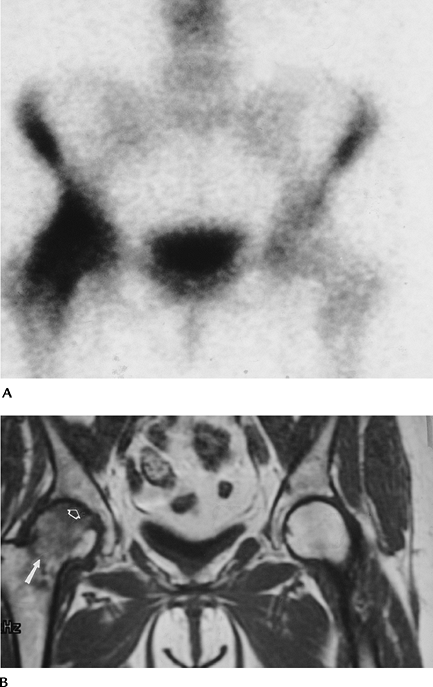

FIGURE 4-32 Routine radiograph was normal. (A) Radionuclide scan shows increased signal intensity in the right femoral head and neck. (B) Spin-echo T1-weighted image shows a femoral neck fracture (arrow), low-intensity edema pattern, and AVN (open arrow).